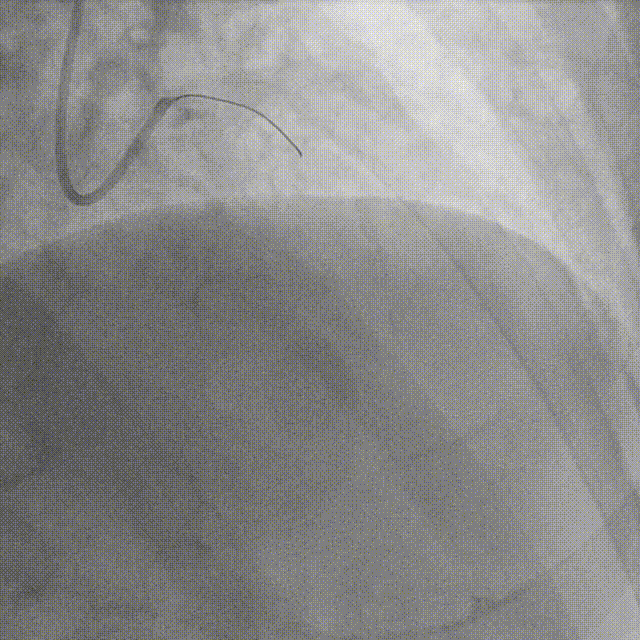

术后冠脉造影:

术后即刻冠脉功能学全面评估:

▶IMR:18;CFR:3.2;FFR:0.89。